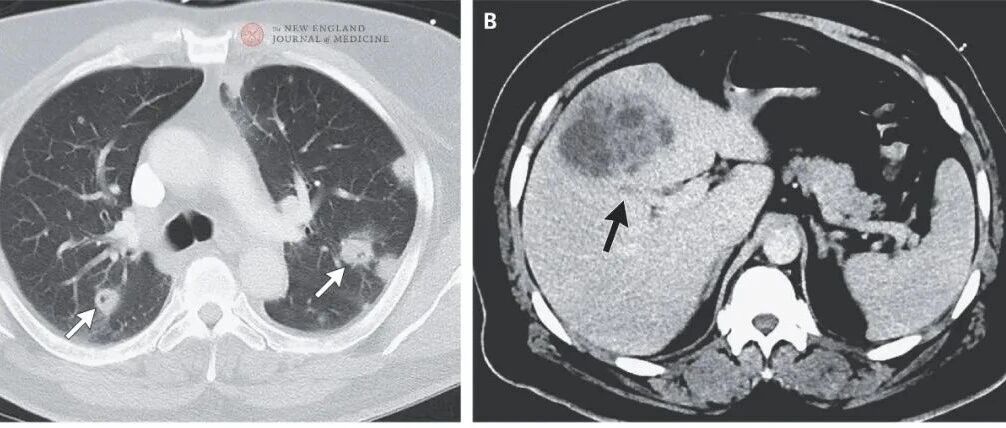

NEJM麻省总医院病例:双肺十余个空洞性结节及肿块,咳嗽发热、右眼一夜失明……致命感染因何迅速经血行...